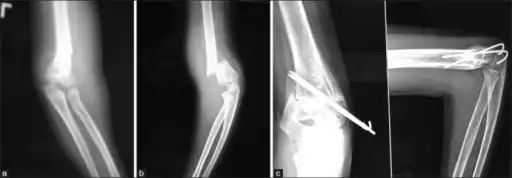

Gartland type III and IV

Gartland III and IV are unstable and prone to neurovascular injury. Therefore, closed or open reduction together with percutaneous pinning within 24 hours is the preferred method of management with low complication rates. Straight arm lateral traction can be a safe method to deal with Gartland Type III fractures. Although Gartland Type III fractures with posteromedial displacement of distal fragment can be reduced with closed reduction and casting, those with posterolateral displacement should preferably be fixed by percutaneous pinning.[3]

Percutaneous pinning

Percutaneous pinning are usually inserted over the medial or lateral sides of the elbow under X-ray image intensifier guidance. There is 1.8 times higher risk of getting nerve injury when inserting both medial and lateral pins compared to lateral pin insertion alone. However, medial and lateral pins insertions are able to stabilise the fractures more properly than lateral pins alone. Therefore, medial and lateral pins insertion should be done with care to prevent nerve injuries around elbow region.[3]

Percutaneous pinning should be done when close manipulation fails to achieve the reduction, unstable fracture after closed reduction, neurological deficits occurs during or after the manipulation of fracture, and surgical exploration is required to determine the integrity of the blood vessels and nerves. In open fractures, surgical wound debridement should be performed to prevent any infection into the elbow joint. All Type II and III fractures requiring elbow flexion of more than 90° to maintain the reduction needs to be fixed by percutaneous pinning. All Type IV fractures of supracondylar humerus are unstable; therefore, requires percutaneous pinning. Besides, any polytrauma with multiple fractures of the same side requiring surgical intervention is another indication for percutaneous pinning.[3]